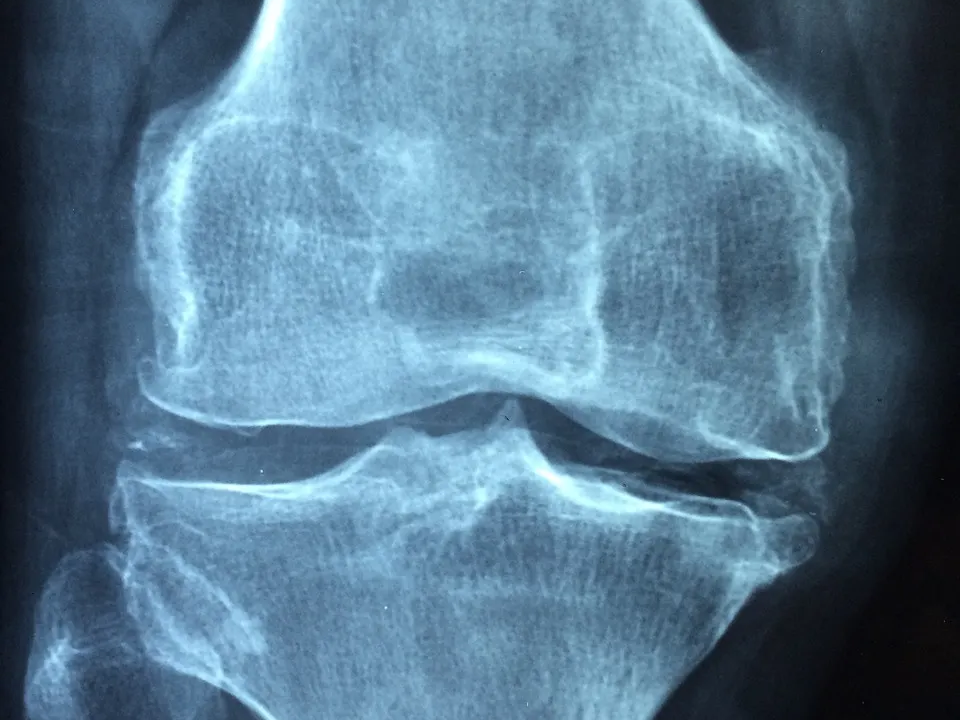

콘드로이친은 특히 골관절염의 증상을 완화하는 데 도움이 됩니다. 연골의 여러 구성 요소의 합성을 증가시키고 연골의 분해를 방지하여 통증을 완화합니다. 특히 무릎 통증에 효과가 있다고 알려져 있습니다. 여러 연구에서 콘드로이친 복용이 통증을 약 20% 감소시킨다고 보고되었습니다. 또한, 연골을 보호하고 재생하는 데도 효과가 있습니다.